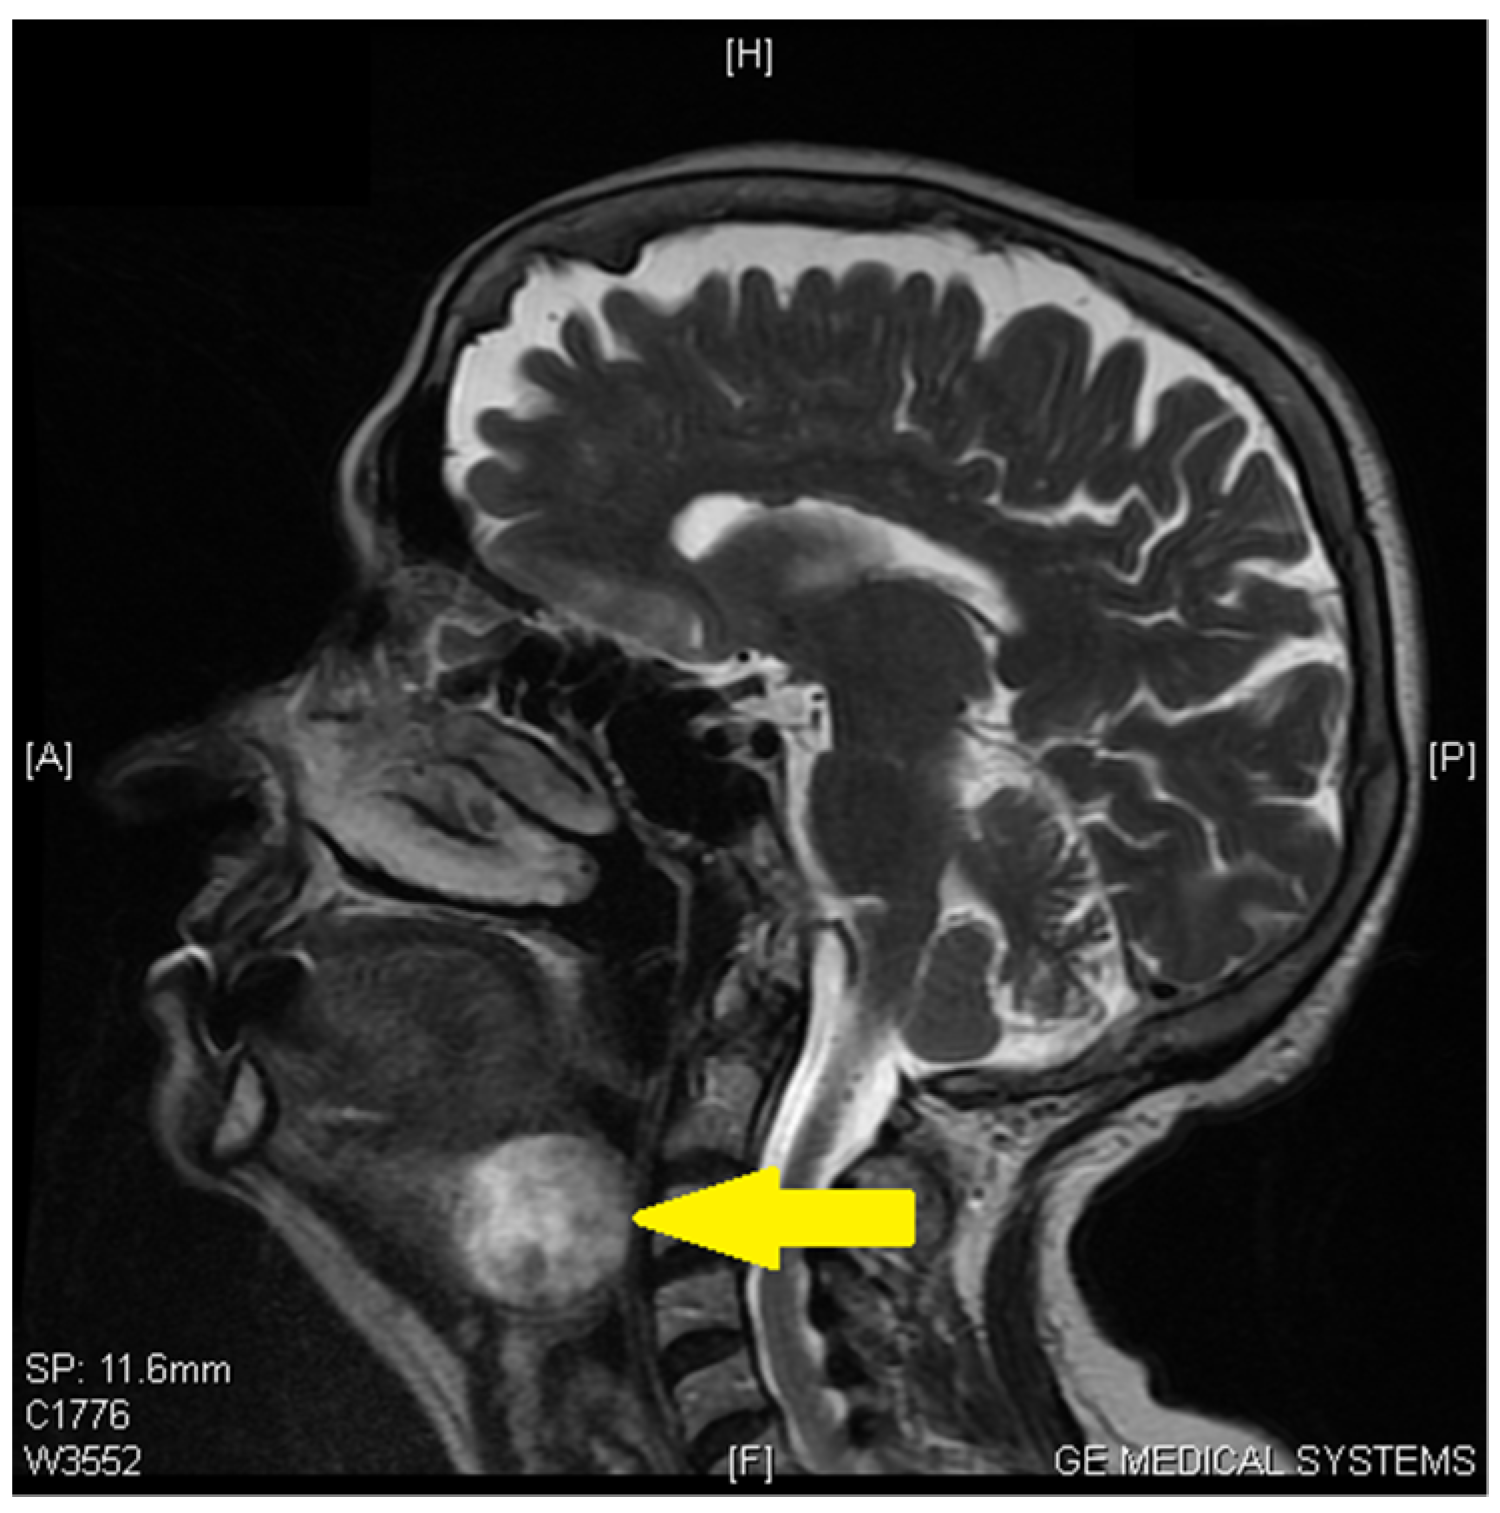

Tongue Base Ectopic Thyroid Tissue—Is It a Rare Encounter?

2. Case Report